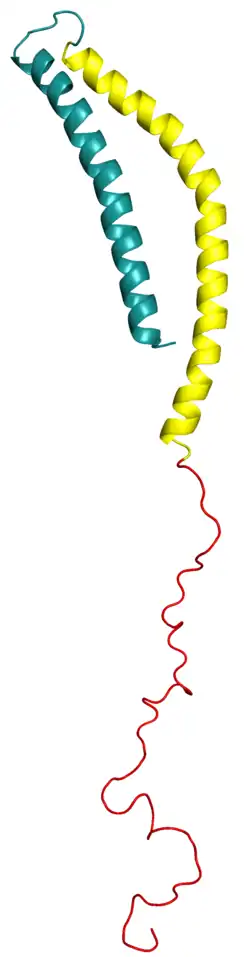

Alpha-synuclein, a protein encoded by SNCA gene mutations, is the main component of the Lewy bodies that accumulate in the brains of people with PD.[48] Alpha-synuclein activates ataxia telangiectasia mutated, a major DNA damage-repair signaling kinase.[54] In addition, alpha-synuclein activates the non-homologous end joining DNA repair pathway. The aggregation of alpha-synuclein in Lewy bodies appears to be a link between reduced DNA repair and brain-cell death in PD.[54] Major genetic risk factors that do not contribute to Lewy bodies include LRRK2 and PRKN.[55]

One mechanism causing brain cell death results from abnormal accumulation of the protein alpha-synuclein bound to ubiquitin in damaged cells. This insoluble protein accumulates inside neurons forming inclusions, known as Lewy bodies.[65][71] These bodies first appear in the olfactory bulb, medulla oblongata and pontine tegmentum; individuals at this stage may be asymptomatic or have early nonmotor symptoms (such as loss of sense of smell or some sleep or automatic dysfunction). As the disease progresses, Lewy bodies develop in the substantia nigra, areas of the midbrain and basal forebrain, and finally, the neocortex.[65] These brain sites are the main places of neuronal degeneration in PD, but Lewy bodies may be protective from cell death (with the abnormal protein sequestered or walled off). Other forms of alpha-synuclein (e.g. oligomers) that are not aggregated into Lewy bodies and Lewy neurites, may in fact be the toxic forms of the protein.[72][71] In people with dementia, a generalized presence of Lewy bodies is common in cortical areas. Neurofibrillary tangles and senile plaques, characteristic of Alzheimer's disease, are uncommon unless the person has dementia.[68]

A vaccine that primes the human immune system to destroy alpha-synuclein, PD01A, entered clinical trials and a phase one report in 2020 suggested safety and tolerability.[211][212] In 2018, an antibody, PRX002/RG7935, showed preliminary safety evidence in stage I trials supporting continuation to stage II trials.[213]